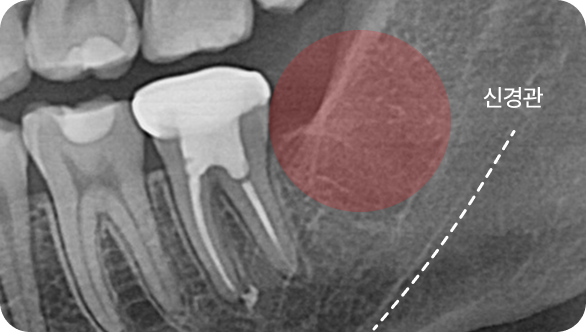

더블보드 전문의 설계는 다릅니다.

더블보드 전문의는 치아교정부터 고난도 치료까지 못하는 진료없이 다수의 임상 경험으로 만족도 높은 결과를 선사합니다.

연세아이돌치과교정과는 11년차 치과교정과 & 통합치의학과 더블보드 전문의가 직접 진료합니다.

단순한 치료를 넘어 일상의 완성을 설계하는

통합 진료 솔루션

단순한 치료를 넘어 환자의 마음을 헤아리는 것에서 연세아이돌치과의 진료는 시작됩니다.

치과교정과 전문의의 심미적 안목과 통합치의학과 전문의의 포괄적 진단이 만나는 곳.

연세아이돌치과교정과의 일반진료는 단순히 질환 부위만을 바라보지 않습니다.

치아 하나가 전체 구강 구조와 조화를 이루는지,

환자분의 식습관과 생활 패턴에 장기적으로 어떤 영향을 미칠지까지 치밀하게 계산합니다.